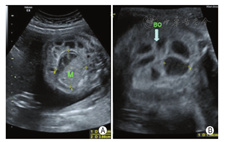

孕妇,31岁,孕2产1,孕期体健,否认孕期用药史,育有一女,2岁体健。孕26+3周行胎儿产前系统超声检查,超声显示:单活胎,生长指标可,羊水过多;小肠管广泛扩张、积液,内径最宽处约1.4 cm;胎儿腹内混合性团块,大小约4.2 cm×3.7 cm×3.2 cm,较固定,与周围组织分界不清;扩张肠管远端显示不满意。超声诊断:胎儿肠管扩张,小肠肠管狭窄或闭锁可能,继发性胎粪性腹膜炎?远端肠管显示不满意(图1)。后陆续进行胎儿超声心动图检查、定期孕期保健及超声随诊,未发现胎儿伴发其他畸形及染色体异常。在当地医院分娩一男婴,出生时即发现全腹膨隆伴口唇发绀,大便未解。全腹CT示:肠管明显扩张,直肠及乙状结肠空虚状伴腔内密度较高,腹腔内多发钙化灶。出生后2 d上述症状不减,遂转至我院小儿外科,门诊拟"①新生儿肠梗阻:先天性肠闭锁?胎粪性腹膜炎?②新生儿肺炎"收住入院。腹部X线检查示:肠腔积气积液。超声检查:房间隔缺损,肝、胆、脾、胰、双肾、输尿管、膀胱未见明显超声异常,腹腔内见多发钙化灶,肠管广泛扩张,最宽处约2.2 cm,考虑肠梗阻、继发性胎粪性腹膜炎可能。结肠造影示:小肠梗阻;结肠管腔较细,结肠袋未显示,结肠细小症?(图2A)。